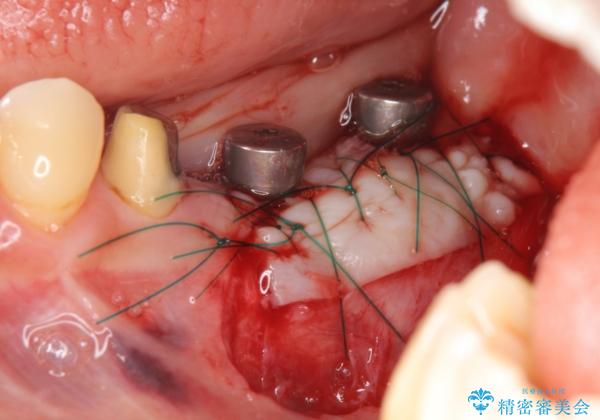

遊離歯肉移植術を併用した、破折歯のインプラント治療

- 他院で根の治療まで終え、違和感が取れず相談に来院されました。

当該歯を精査したところ、歯根に破折が見られ抜歯を余儀なくされました。

抜歯後、インプラントを用いて咬合機能を回復すると共に周囲に強固な角化歯肉を移植することによりより長期にわたり安定したインプラント周囲環境となるよう治療を計画します。

インプラント周囲の角化歯肉が存在することにより、歯ブラシがしやすくなりインプラントにトラブルが起きる確率を減らしより長期的な予後を望むことができます。